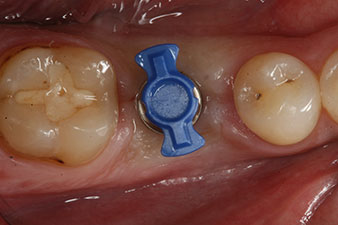

SmartPeg

Fig. 4: SmartPeg measuring posts screwed on to measure the implant stability quotients with the integrated W&H Osstell ISQ module.

The torque used for the machine-driven placement was 43 Ncm. In addition, after screwing a measuring post (SmartPeg) specially matched to the implant, the ISQ value was measured with the probe of the W&H Osstell ISQ module.

This module is an optional extra for the W&H Implantmed and is docked to the implantology motor (see Fig. 11). The dimensionless ISQ value immediately after insertion was 64 orovestibular and 68 mesiodistal (maximum value = 100).

These values could have indicated open healing or even immediate restoration. Due to the insufficient crestal bone volume at the implant, the region was augmented with the bone chips collected during preparation of the implant bed and sutured to exclude saliva.